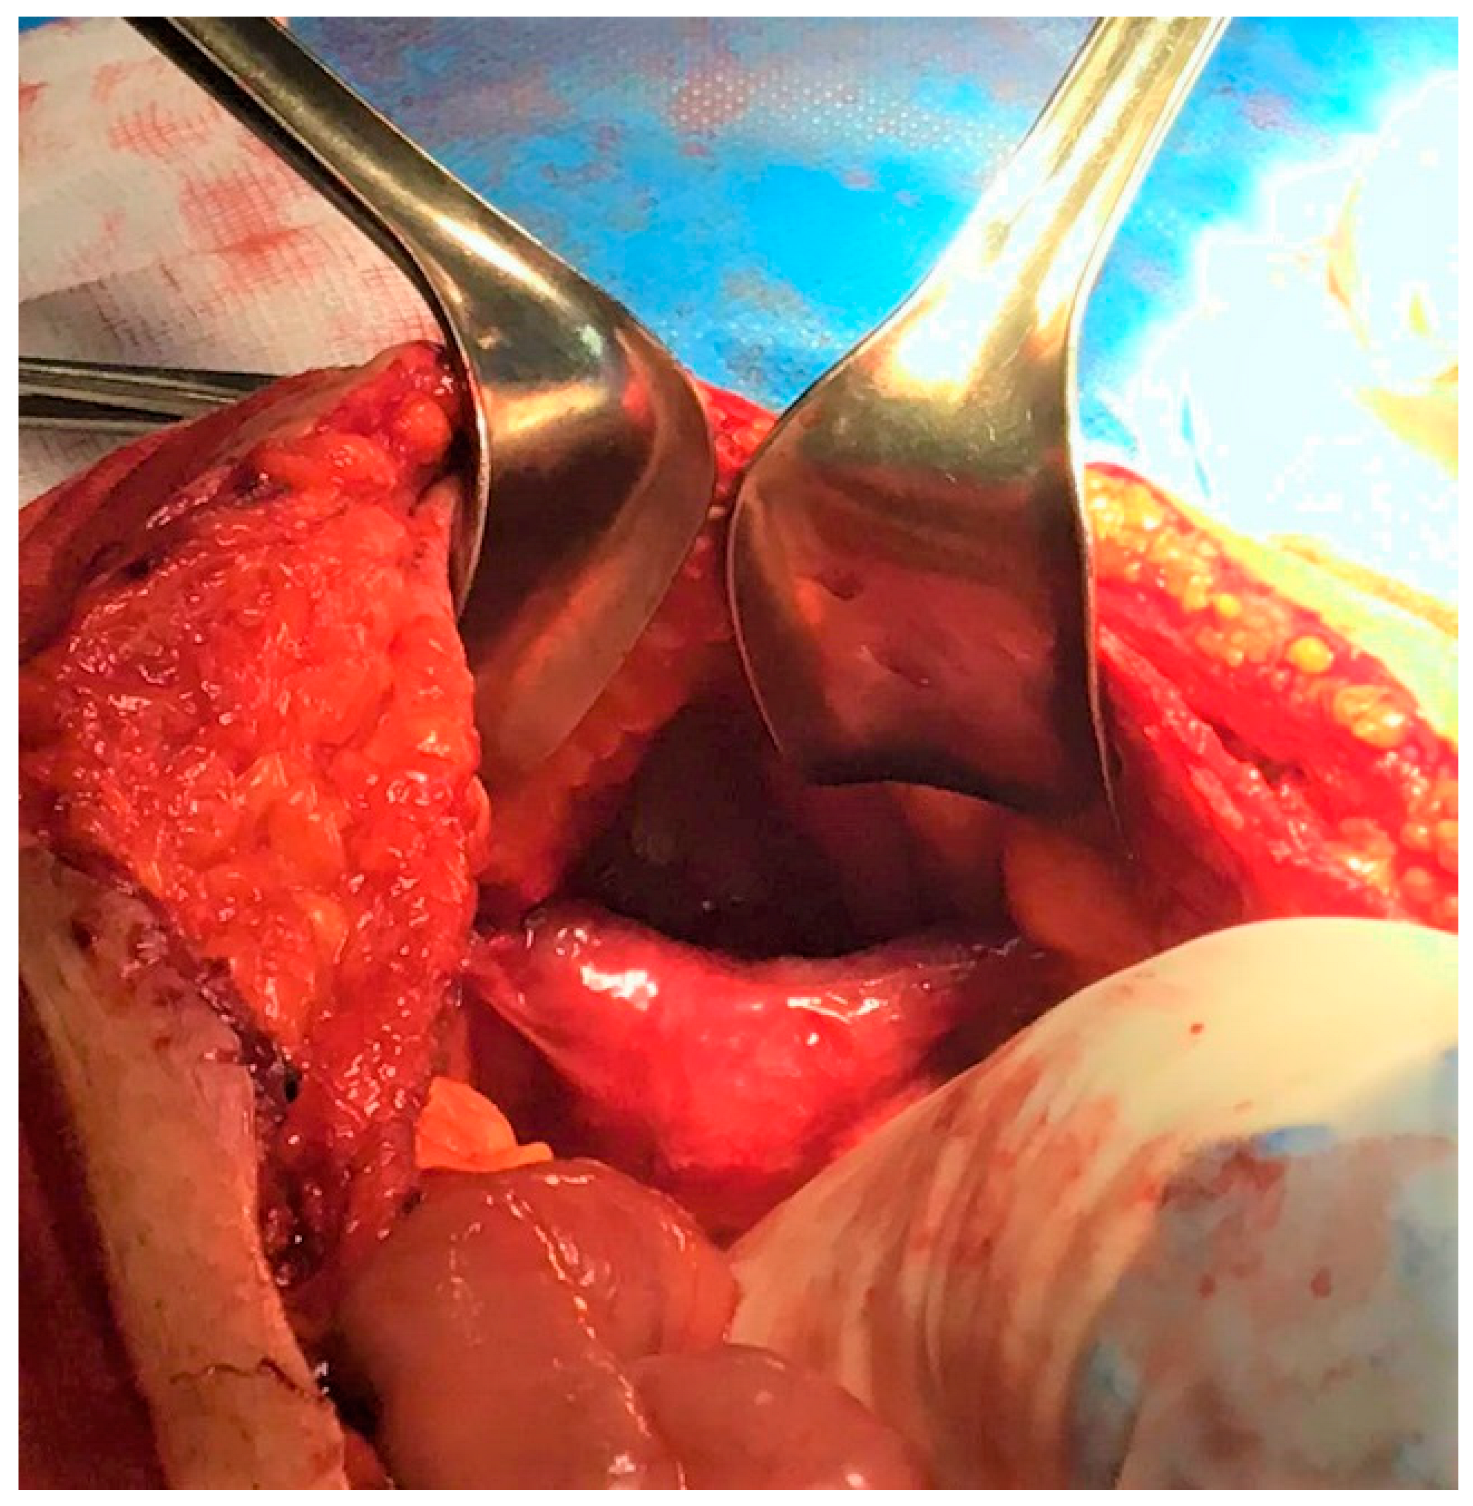

3. Case Report